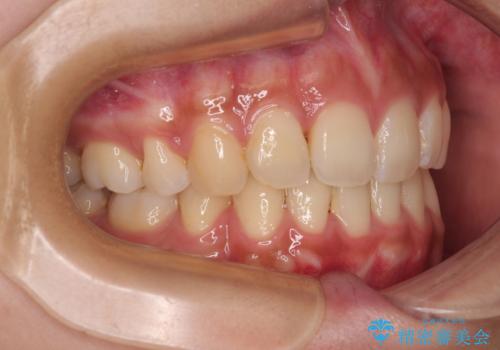

- 前歯の突出感とデコボコを気にして来院された患者様です。

奥歯の噛み合わせをみると、上顎歯列が全体的に前突している状態であり、この咬み合わせのまま歯列を整えると出っ歯になってしまう可能性がありました。

上下の前歯が接触する仕上がりとなったので、横顔の印象が大幅に改善されました。